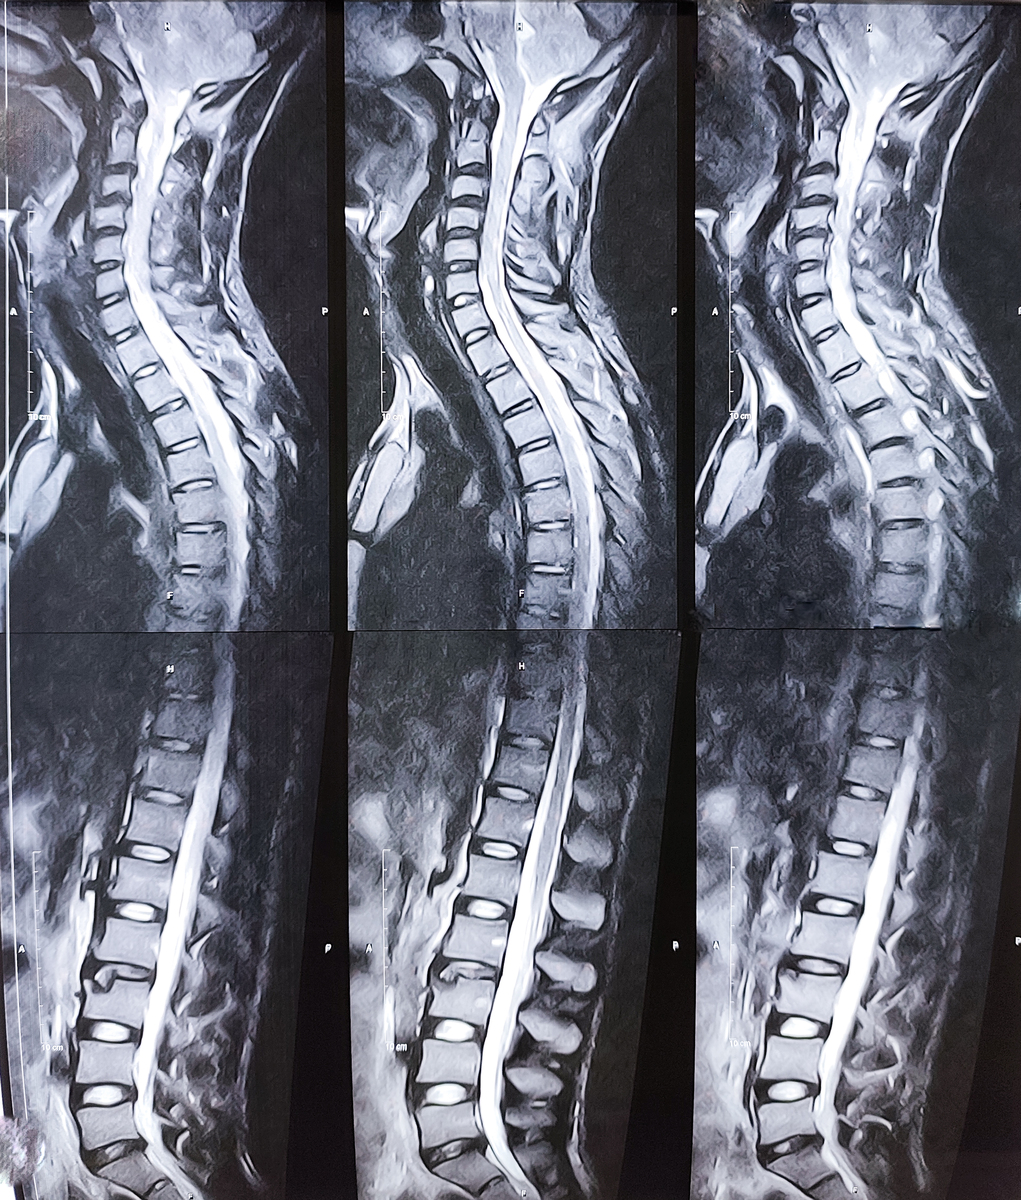

脊柱受力测量是一种评估人体脊柱受力的方法。通过使用压力传感器和电子设备,可以测量脊柱在不同位置和方向上的受力情况。这种测量可以帮助医生和康复专家诊断和治疗脊柱相关的疾病和损伤,同时也可以优化人体姿势和运动技能,预防脊柱损伤和疼痛。脊柱受力测量通常在康复中心、运动医学中心和研究实验室中进行。